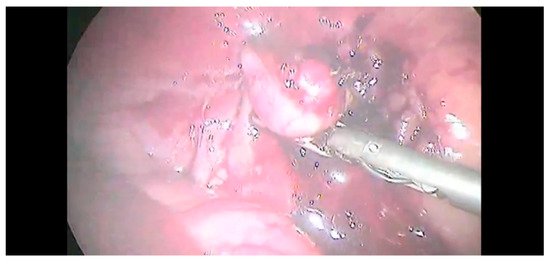

2.2. Surgical Procedure